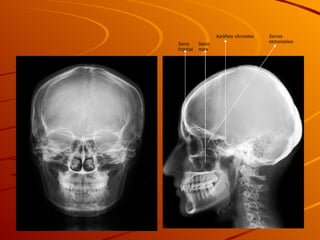

Apófisis clinoides Seno max Seno frontal Senos etmoidales

Apófisis clinoides Senomax Seno frontal Senos etmoidales